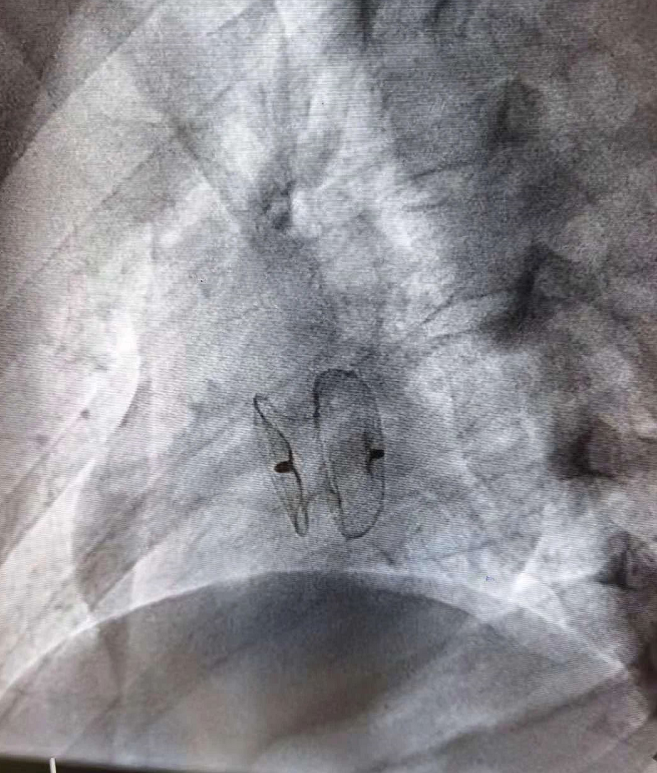

室间隔缺损偏心封堵器

房间隔缺损封堵器

房缺封堵器影响表现